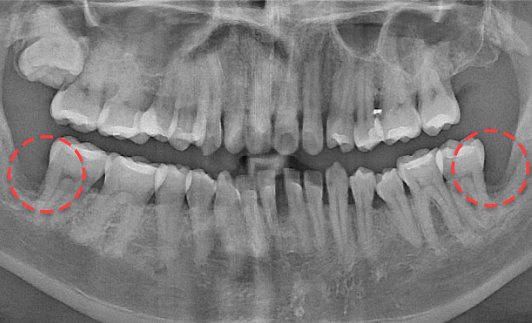

• BEFORE

양쪽 하악 매복 사랑니 발치 Before X-Ray

치료시작일

2019.11.05

AFTER

양쪽 하악 매복 사랑니 발치 After X-Ray

치료종료일

2020.12.24

양쪽 하악 매복 사랑니 발치